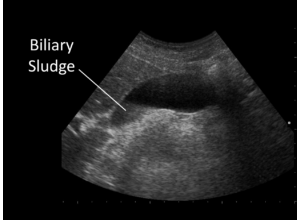

El lodo biliar se forma cuando estos componentes se agrupan y precipitan dentro de la bilis, convirtiéndola en una sustancia más espesa y densa. En una ecografía, el lodo biliar aparece como una sustancia que refleja el ultrasonido, lo que permite identificar su presencia en la vesícula biliar. Aunque a veces no causa síntomas, el lodo biliar puede ser un precursor de problemas más serios, como los cálculos biliares y la inflamación de la vesícula biliar.